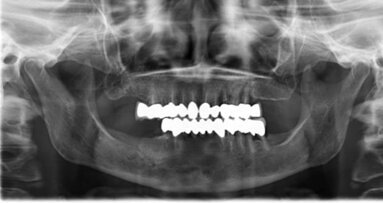

ANN ARBOR, Mich., Stati Uniti d’America – Dentisti e ingegneri biomedici hanno per la prima volta trattato un paziente con un grave difetto parodontale utilizzando uno scaffold polimero bioassorbibile, personalizzato stampato in 3D. Anche dopo il fallimento del sito, 13 mesi dopo la terapia, i ricercatori credono che i biomateriali stampati in 3D possono offrire, in futuro, un’alternativa alle procedure tradizionali per la ricostruzione parodontale.

La procedura è stata eseguita su un paziente di 53 anni di sesso maschile con diagnosi di parodontite aggressiva generalizzata. A causa delle limitate opzioni di ricostruzione, è stato scelto, al fine di preservare la dentatura del paziente, un approccio bioingegneristico che comporta l’impianto di una struttura in 3D per riempire il difetto parodontale, come riferito dai ricercatori.

I ricercatori hanno raccontato che il sito trattato è rimasto intatto per 12 mesi, a dimostrazione di un guadagno di 3 mm di attacco clinico e della copertura parziale della radice, senza segni di infiammazione cronica o deiscenza. Tuttavia, 13 mesi dopo la terapia, la struttura si è esposta.

Anche se questa prima applicazione di uno scaffold stampato in 3D non ha avuto successo, nel lungo periodo, i ricercatori hanno concluso che ulteriori ricerche in merito all’applicazione di tale tecnologia e al miglioramento del riassorbimento potrebbero portare a un nuovo e più personalizzato approccio clinico alla medicina rigenerativa orale.